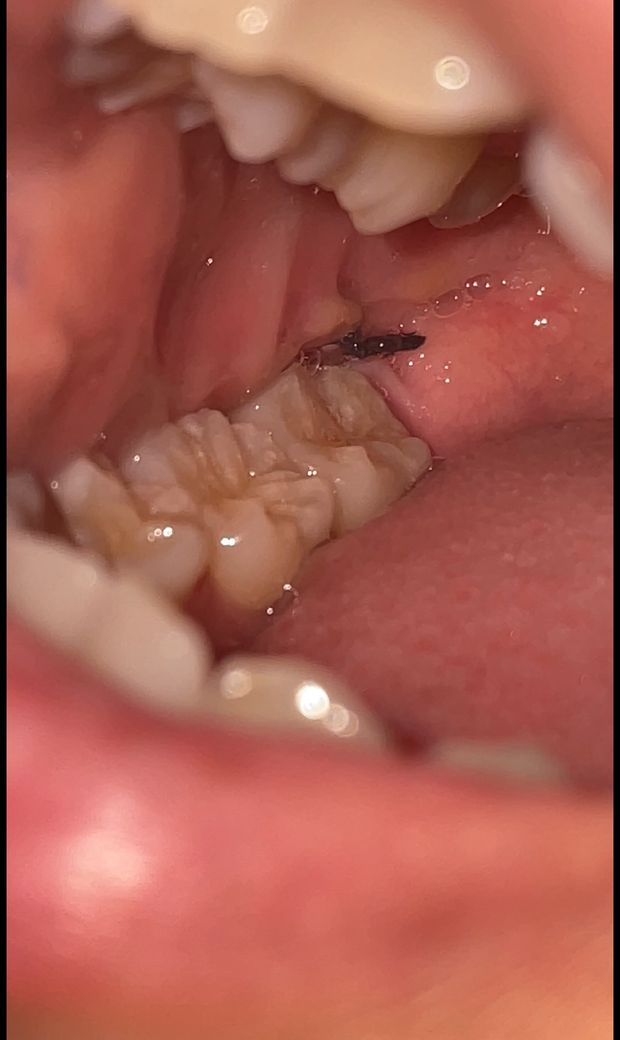

수평매복사랑니 발치 4일차 염증인가요??

수평매복사랑니 발치 후 4일차이고 살짝 열감 있는데 통증은 심하진 않아요 저거 노란색 혹시 염증인가요? 염증이면 온찜질 안되나요? 얼굴이 3일차때처럼 너무너무 부어서요

사진만 봤을 때에는 잘 낫고 있어보입니다. 붓기 등은 시간이 지나면서 점차 나아질 것 입니다.

사진상으로 염증이나 문제가 잇거나 그렇진 않으니 자극만 가지 않도록 해주시면될것같습니다.

염증의 양상인데 붓기도 아직 있으면 냉찜질과 온찜질 번갈아 가면서 해주세요 더 중요한 건 약 잘 챙겨먹는겁니다